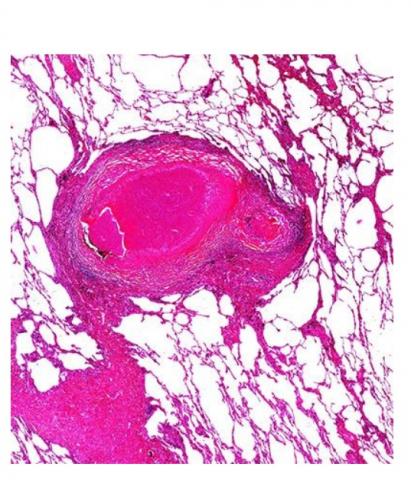

Tissu pulmonaire humain d'un patient tuberculeux avec lésion granulomateuse nécrosante centrale